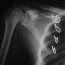

- TREATMENT: Right Scapulothoracic arthrodesis with wiring ribs 3 - 6

and ICBG: June of 1994 Left Scapulothoracic arthrodesis with wiring ribs

3 - 6 and ICBG: June of 1995

- FOLLOW-UP: Markedly improve RPM with active abduction of 125 - 140

degrees and improved motor strength of both upper extremities.